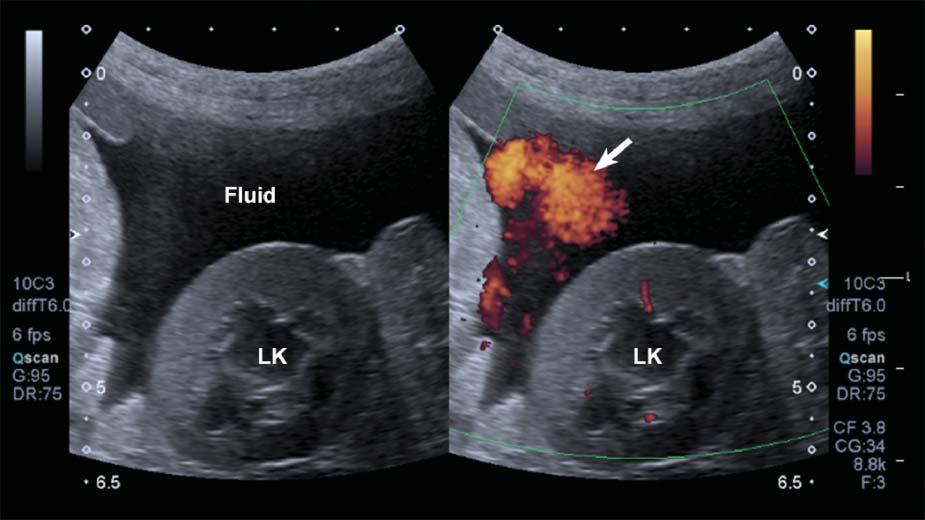

DopplerFlashArtifact

Rapidmovementofthepatient’sbody,ofastructural component(e.g.,heartorarterialpulsation),orofthe probemightleadtoDopplershiftsbeinginterpreted bythesystemasbloodflow.Aspuriousappearance

ofbloodflowisdisplayed,limitingtheassessmentof truevessels.Thisartifacttendstobemoreapparentin fluid-filledstructuresandwithascites(Figure1.25).

Figure1.25. Flash. SpuriousechoesoftenappearwhenusingpowerDopplerinmovingpatientsorwhenascitesispresent, limitingtheassessmentthetissueperfusioninthesecases.LK,leftkidney.